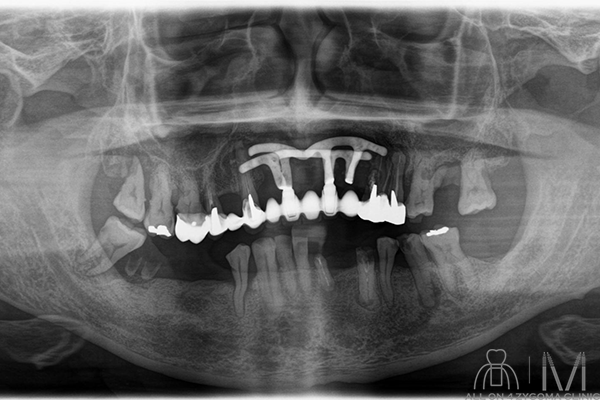

術後パノラマ画像所見

4本のザイゴマインプラントと4本のノーマルインプラントに8本のアバットメントを認める。同部にはテンポラリーシリンダーが装着されている。上下とも骨整形を示唆する所見を認める。